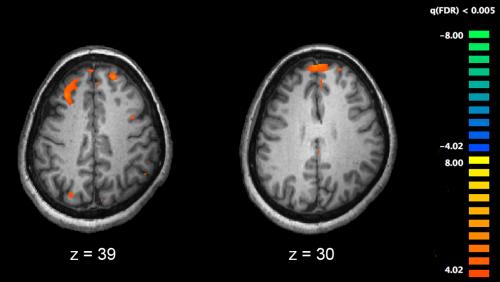

The reason is that brain injury operates a bit like the property market in that the three most important things to consider are location, location and location. When nerve pathways are damaged, those brain areas served by those pathways may wither or have their functions taken over by other brain regions. Nerve pathways are also called ‘white’ pathways or ‘white matter’ because they are covered by an insulating sheath of myelin and appear white to the naked eye.

The challenge is to determine the location of key ‘scaffold’ pathways and to understand what makes them so vulnerable and important. This is not an easy task given the total length of nerve pathways in the average 20-year old human brain is 160,000 km. A recent study provides new findings on the brain’s network scaffold that will help inform clinicians about the neurological impacts of brain diseases such as multiple sclerosis, Alzheimer’s disease and brain injury.